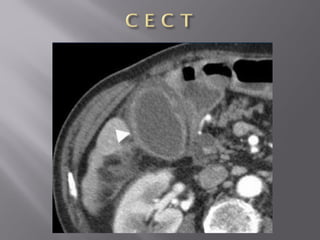

• 39.

 Cholecystitis  Occurswhen a calculus obstructs the cystic duct. The trapped bile causes inflammation of the gallbladder wall.  U S G is the preferred imaging method for the evaluation of cholecystitis, also allowing assessment of the compressibility of the gallbladder.  The diagnosis of a hydropic gallbladder is solely made on the non-compressability of the gallbladder.